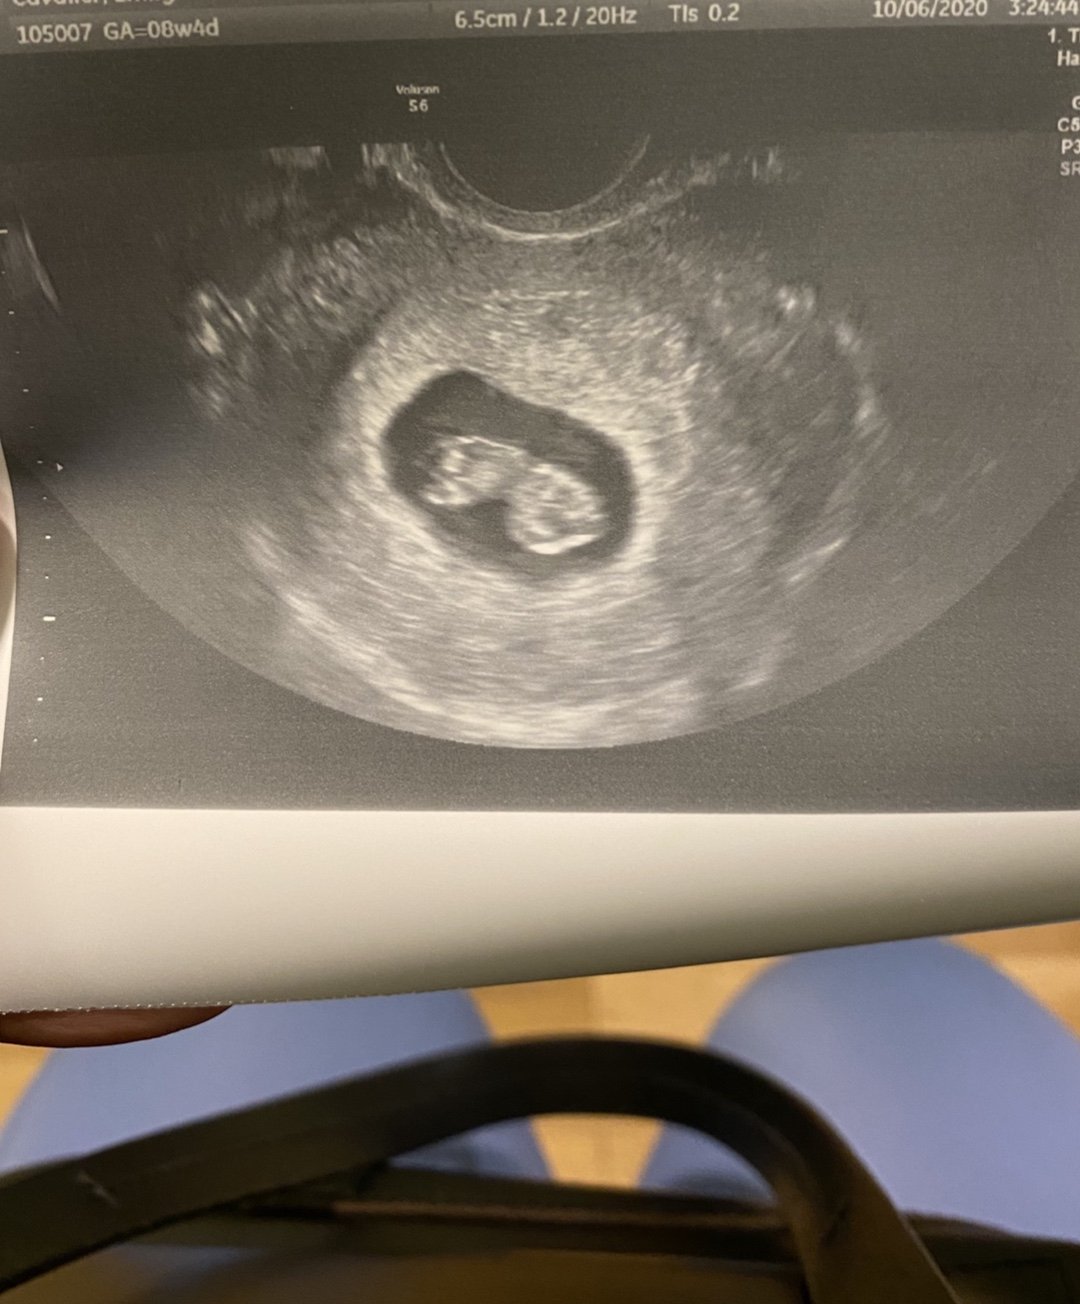

• 🍁 Estimated Due Date/Weeks + Days: 5/14 (8+3)

πŸ•˜ Upcoming appointments: Two tmw (Tues.), a virtual with the genetic counselor and an 8 wk u/s followed by meeting with my OB

• Little nugget is doing great. Measuring perfectly (1 inch big now!) HB 180. 😍